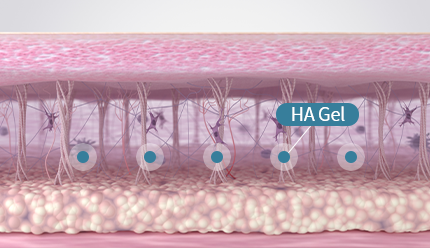

70% of Collagen Structure

Glycine, proline, and lysine account for approximately 70%

of the collagen structure. During fibroblast metabolic activity,

these amino acids stimulate fibroblasts to promote collagen

production and support collagen synthesis, helping improve

skin firmness and structural integrity.

Elasticity Enhancement

Elasticity Enhancement